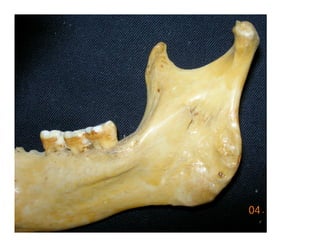

Este documento describe los principios de construcción de la arquitectura craneofacial, incluyendo el metamerismo, la simetría y la paquimería. Explica la organización peri-cavitaria del cráneo a través de columnas y vigas, y analiza las diferentes fascias profundas del cuello. También destaca la importancia de conocer la irrigación ósea con orientación quirúrgica, mencionando los principales aportes vasculares y suplementarios así como el origen, trayecto y retorno venoso de la carót